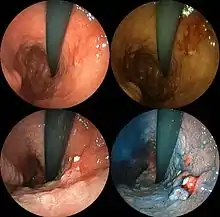

![]() | |

| A stomach ulcer that was diagnosed as cancer on biopsy and surgically removed | |